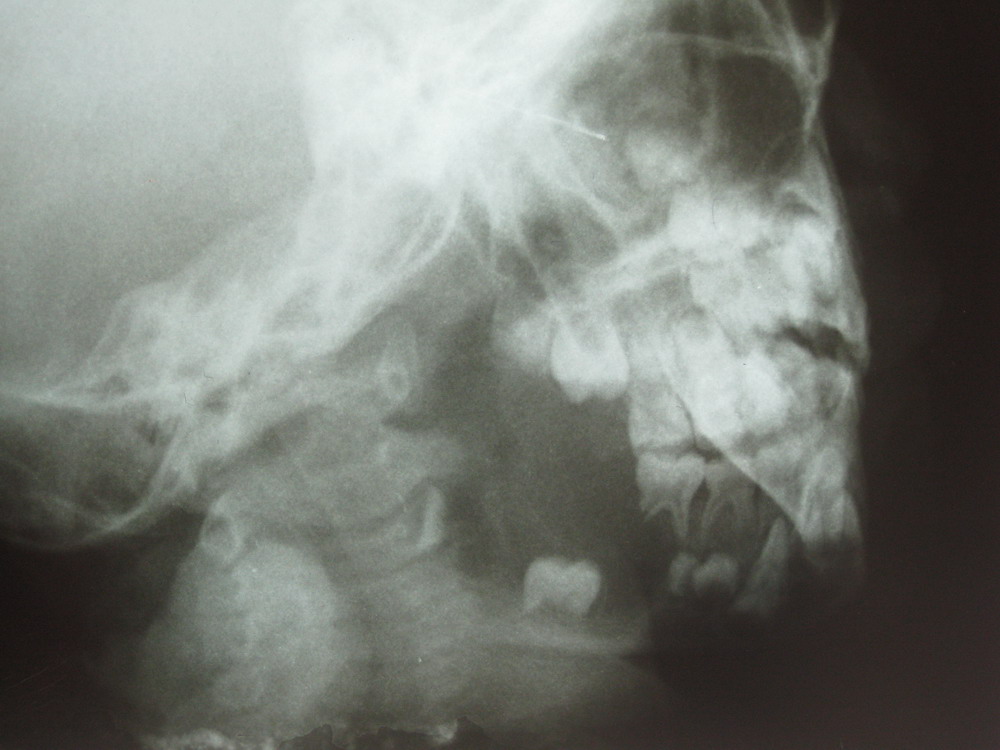

小儿面部肿胀一周

左侧下颌体部溶骨性骨质硬坏,破坏边界欠清,边缘无显著硬化,牙列不齐,牙根亦有骨质溶解,考虑下颌骨牙源性囊肿可能性大,建议ct检查,患者症状急发,考虑合并感染,不知有否其他症状如疼痛,发热等

左下颌骨呈溶骨性破坏,边界尚请。左恒牙牙根部骨质破坏、缺损。结合症状考虑含牙囊肿并感染。建议ct带除外肿瘤样变。

左侧下颌体部溶骨性骨质硬坏,破坏边界欠清,边缘无显著硬化,牙列不齐,牙根亦有骨质溶解,考虑下颌骨糙釉细胞瘤或嗜酸性肉芽肿或牙源性囊肿可能性大

左侧下颌体部及角部溶骨性骨质硬坏,破坏边界欠清,边缘无显著硬化,牙列不齐,相邻牙根亦有骨质溶解吸收,考虑下颌骨糙釉细胞瘤或下颌骨肉瘤,建议结合ct检查。